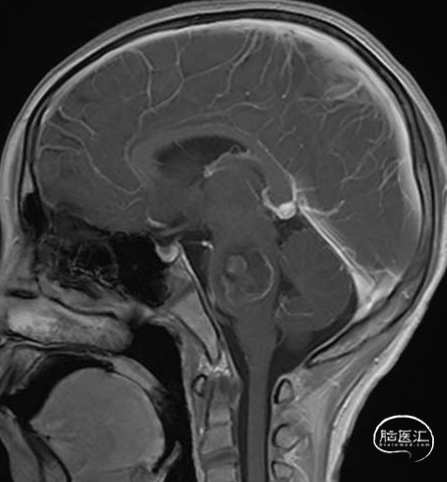

术后MRI